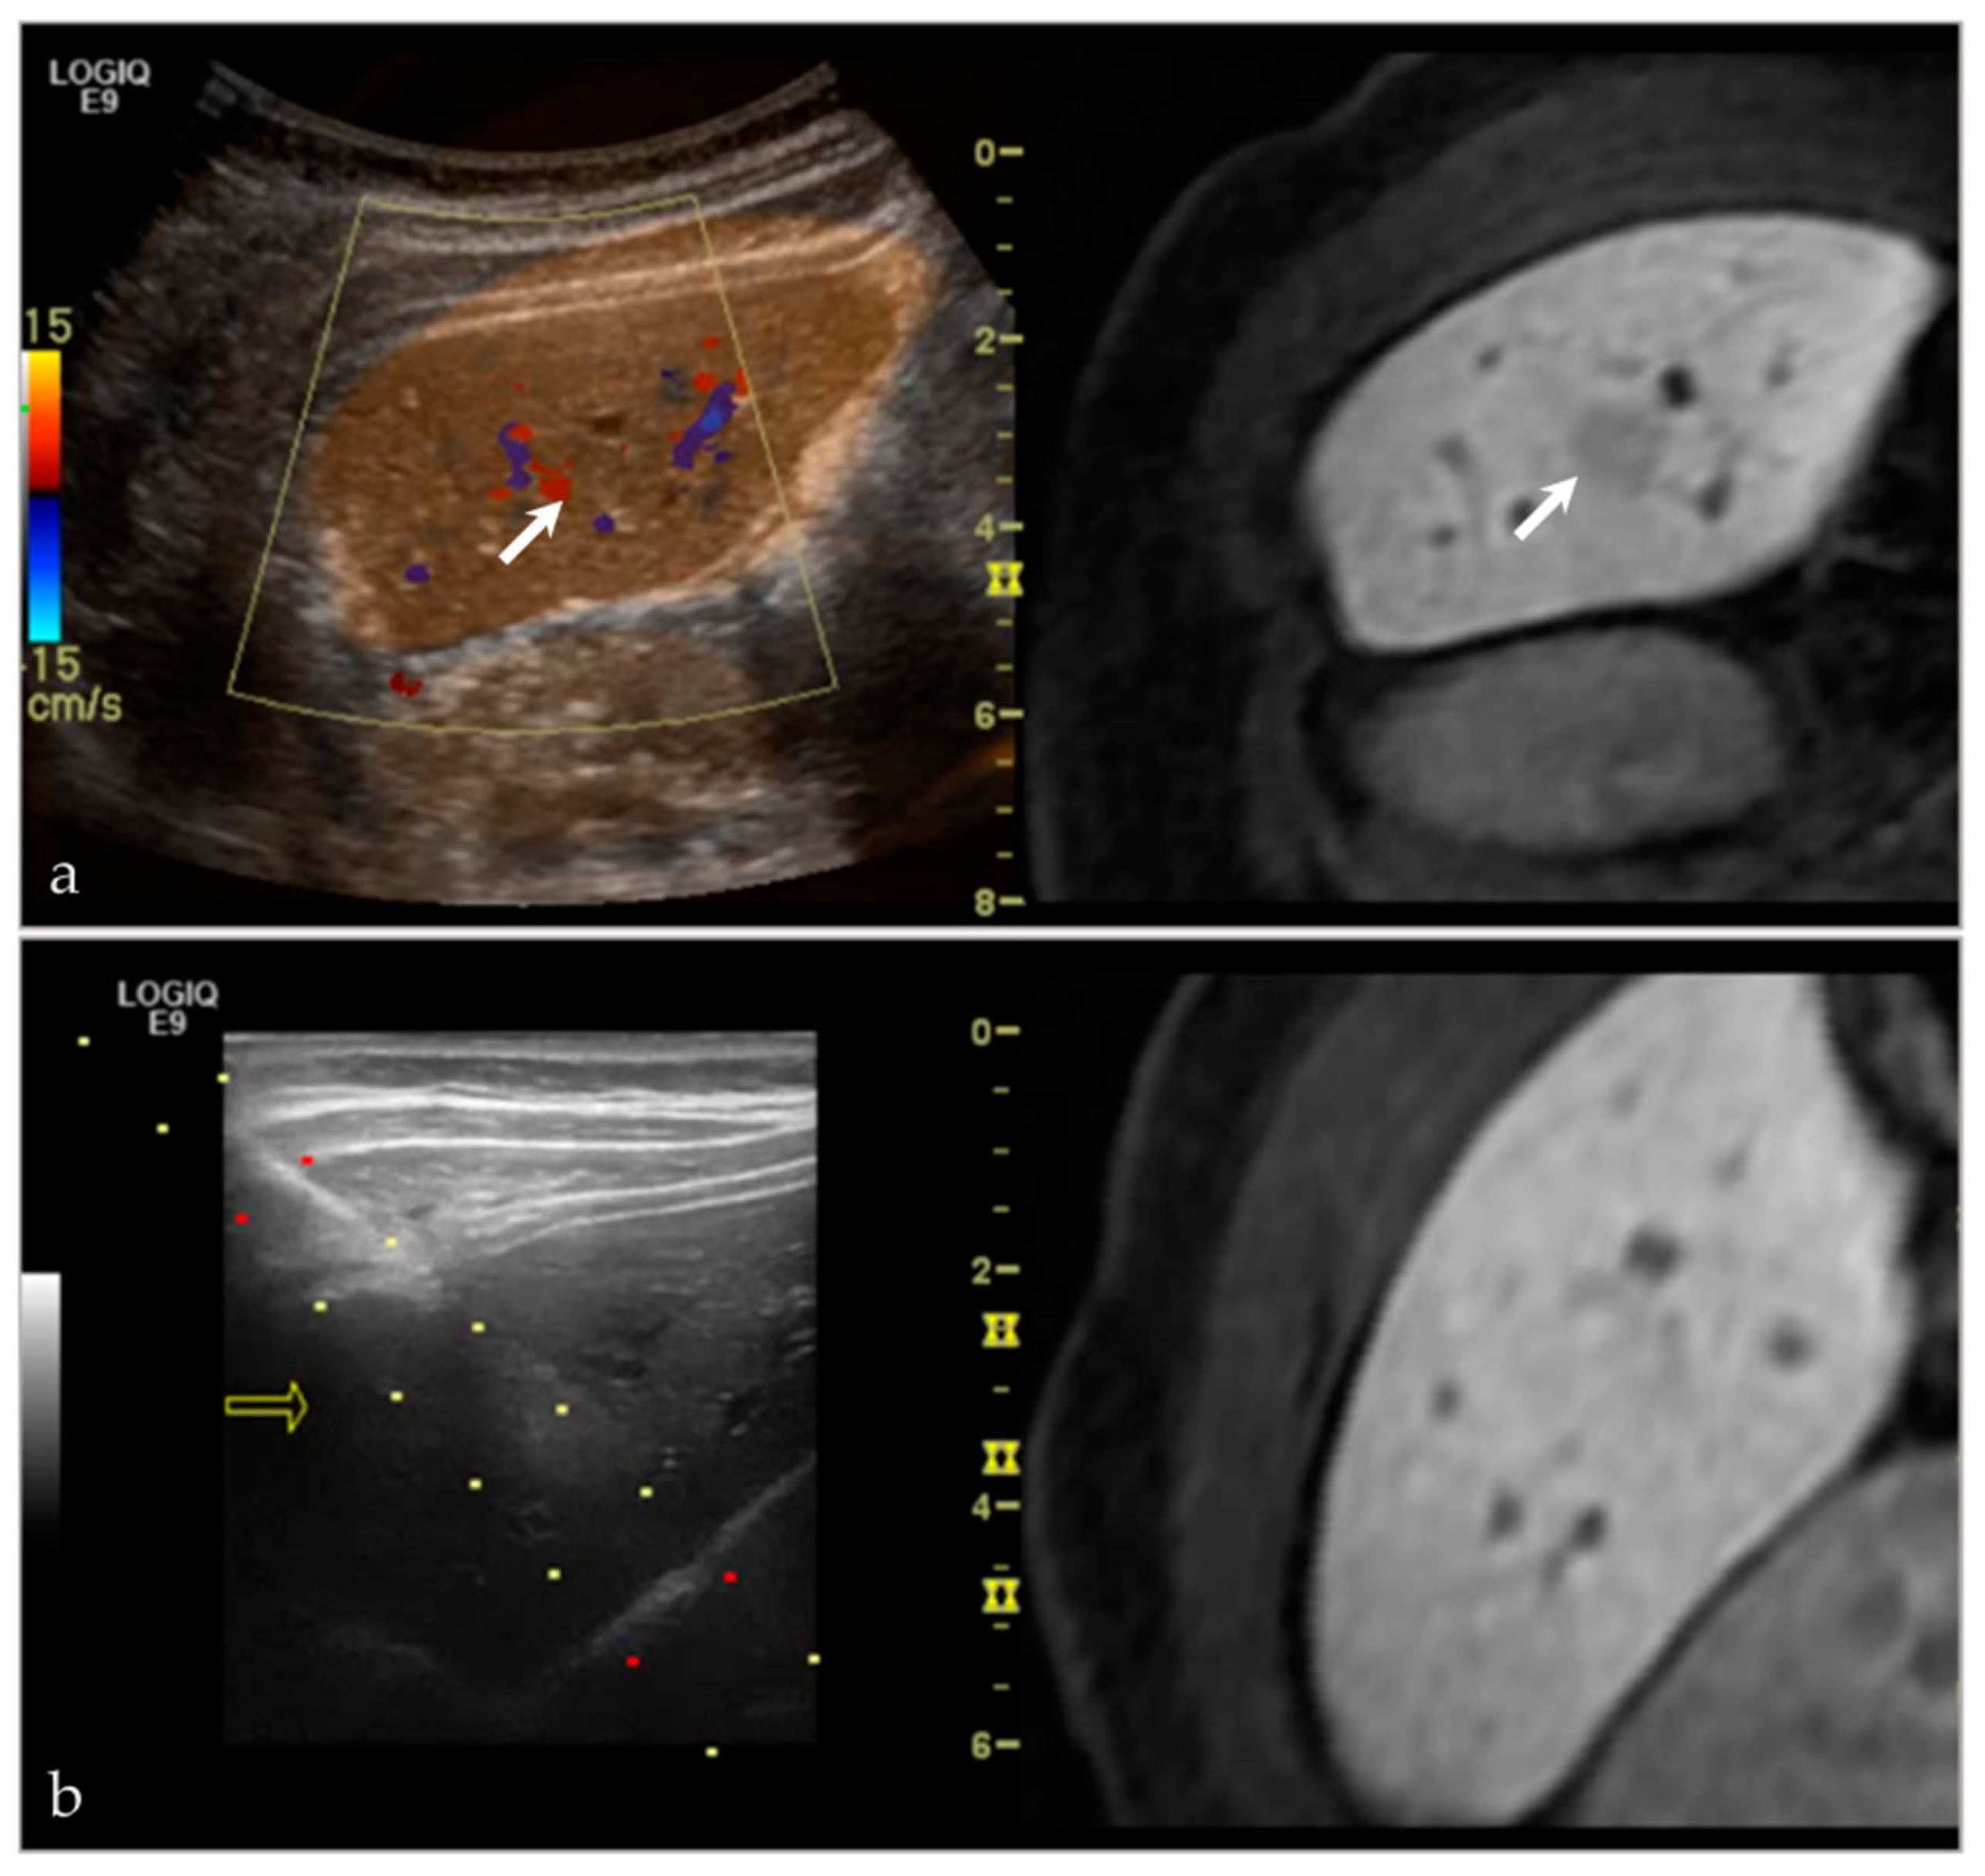

- Lee, K.H.; Lau, V.; Gao, Y.; Li, Y.L.; Fang, B.X.H.; Lee, R.; Lam, W.W.M. Ultrasound-MRI fusion for targeted biopsy of myopathies. Am. J. Roentgenol. 2019, 212, 1126–1128. [Google Scholar] [CrossRef] [PubMed]